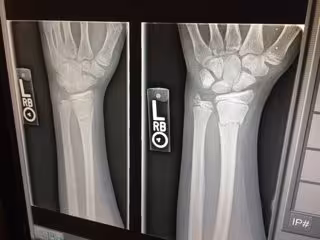

Archivo - Huesos, Radiografía

Archivo - Huesos, Radiografía - NICKWARRILOW/PIXABAY - Archivo